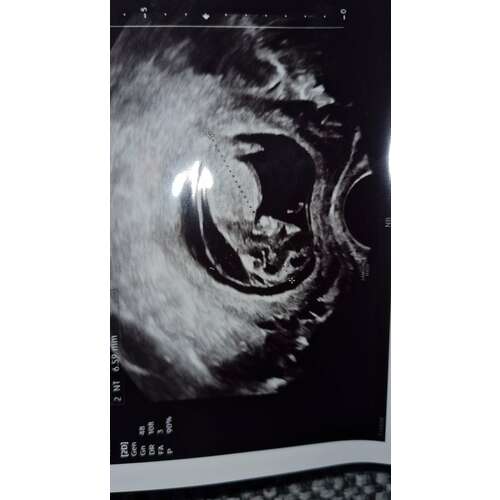

Op basis van de echo foto zou ik er vanuit gaan dat het om het Down Syndroom gaat. De nekplooi is wel echt behoorlijk, daarnaast lijkt het gezichtje van jullie kleintje ook afgeplat en is er mijn inziens geen overduidelijk neusbotje zichtbaar.

Precues zoals het bij ons zoontje ook was, al had ons zoontje het zelfs nog iets minder opvallend naar mijn idee.. en dit bleek inderdaad om het Down Syndroom te gaan.